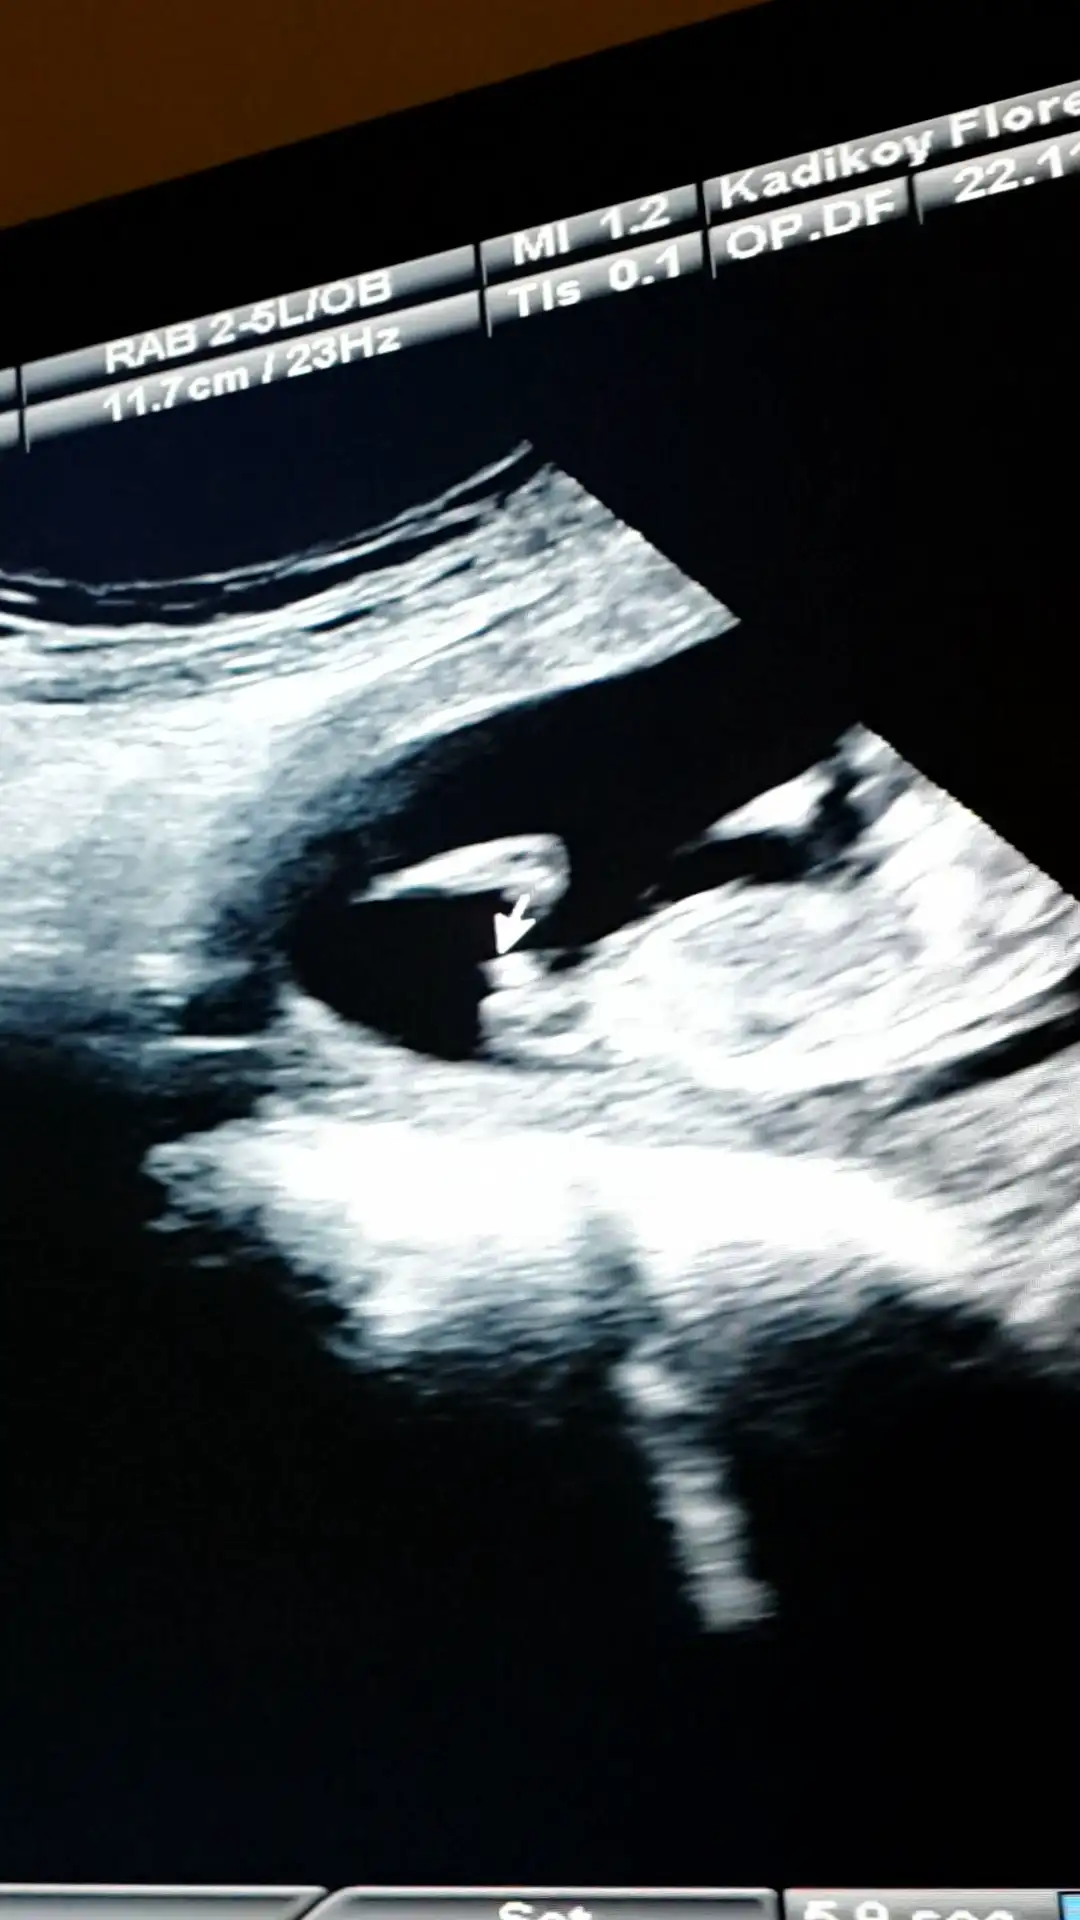

Canim resmini nub teorisi sayfasinda paylasayim bakalim ne dicekler orkidemde orda gorurse cvp verir haber ederimdenizkinub7 .!.:Canim esim bebisi videoya cekmisti ordan kopyaladigim bir resmi ekledim doktorun tam cikintisini isaretleyip gosterdigi yerin resmi. Onuda paylasmak istedim bi bakarsin tekrar doktorla ayni fikirdemisiniz merak ettim senin yorumunudaEki Görüntüle 1311947 Eki Görüntüle 1311948 Eki Görüntüle 1311949